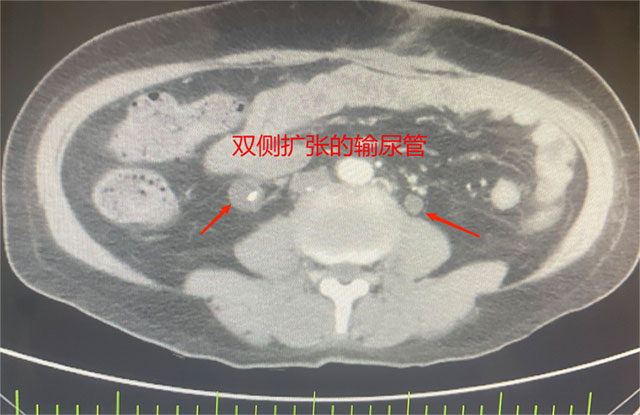

她被确诊为乙状结肠癌,肿瘤已“疯狂”侵犯膀胱、子宫、输尿管等多个盆腔脏器,还伴随不全性肠梗阻。2个月前在外院住院治疗,因手术风险大,外院仅为她做了横结肠造口术缓解梗阻,可术后不幸出现结肠膀胱瘘——小便中混着大便的症状让她痛苦不堪,叠加尿路感染、肿瘤引发的消化道出血,以及尿路梗阻导致的肾功能不全,多重并发症叠加,生活质量跌至谷底。

先是完整切除受肿瘤侵犯的直肠与乙状结肠原发灶,紧接着剥离与肿瘤紧密粘连的子宫及双侧附件并完整移除,随后小心翼翼分离膀胱与周围组织,将受侵膀胱全部切除——前三项切除手术已耗极大精力,团队仍需在腹腔镜下用回肠精心构建新的膀胱通路,确保患者术后排尿功能正常。